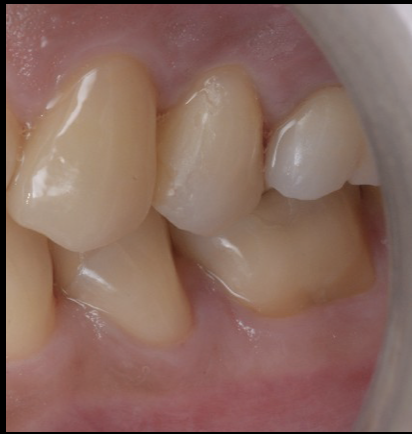

今回の症例も、外科処置を行わずに、歯肉が自然に健康的なラインへ整いました。

その結果、

治療後には歯肉の炎症も消失し、自然な歯肉形態が獲得できました。

治療終了後は以下の改善が得られました。

- 歯肉が健康的なラインに安定

- セラミッククラウンが自然に適合

- 咬合が安定し、日常生活の痛みが消失

- 外科なしで歯を残すことに成功